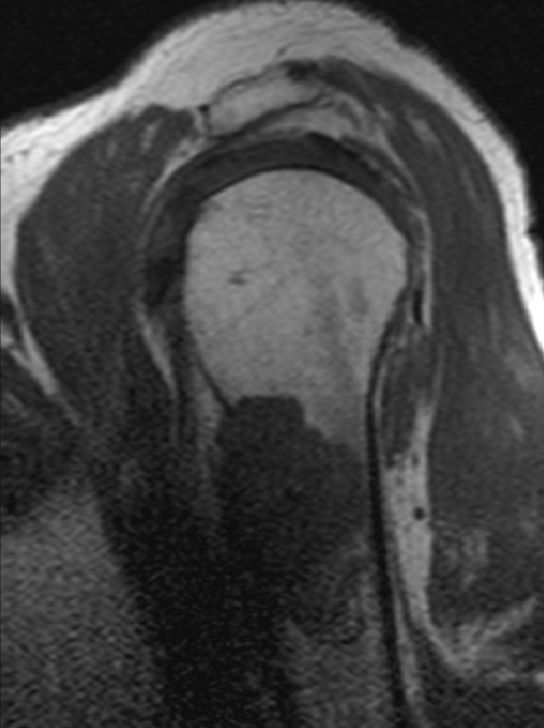

Humerus |

![]() |

![]() | ||||||||||||||||||